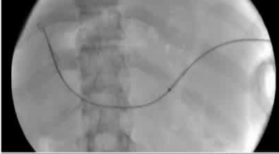

该程序包含以下步骤: 经脾脏入路:在超声引导下,刺穿脾静脉内的一个实质内分支。 在通过脾静脉造影确认了静脉通路后,导管和导丝被推进,以穿过脾静脉并抵达血栓化的门静脉。在门静脉/右门静脉分支处放置圈套器,为TIPS穿刺精准定位。TIPS穿刺圈套器,并穿过圈套器完成TIPS

步骤: 鉴于慢性血栓形成的复杂性: 一种经脾脏途径的门静脉再通术(PVR)。 随后是经颈静脉肝内门体分流术 。